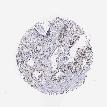

PROSTATE CANCER - Protein expressioni

A mouse-over function shows sample information and annotation data. Click on an image to view it in a full screen mode. Samples can be filtered based on level of antibody staining by selecting one or several of the following categories: high, medium, low and not detected. The assay and annotation is described here.

Antibody stainingi

Antibody staining in the annotated cell types in the current human tissue is reported as not detected, low, medium, or high, based on conventional immunohistochemistry profiling in selected tissues. This score is based on the combination of the staining intensity and fraction of stained cells.

Each image is clickable and will lead to virtual microscopy that enables deeper exploration of all samples and also displays staining intensity scores, fraction scores and subcellular localization as well as patient and tissue information for each sample.

Antibody HPA000427

Antibody CAB004680

Adenocarcinoma, Medium grade

Adenocarcinoma, Low grade

Adenocarcinoma, High grade